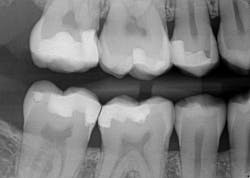

Caries lesions were removed and air abrasion was employed to remove impurities on the unprepared tooth surfaces and create increased surface area for bonding. Preparation of the class II carious lesions revealed demineralization on the adjacent tooth structure (figure 3). When lesions such as these are discovered, dentists are often at a crossroads whether to intervene or monitor the area for progression. It is my experience that these early caries lesions can be predictably arrested with resin infiltration (figure 4), and that no intervention usually results in the progression of caries.

In this case, lateral access was achieved by the preparation of the adjacent teeth as part of the proposed treatment plan. Early caries lesions that are noted on radiographs that are not accessible in cases such as this one can be accessed by placing an orthodontic spacer. This patient was restored with direct composite bonding (figure 5) and these restorations have proven to have a favorable long-term outcome (figure 6).